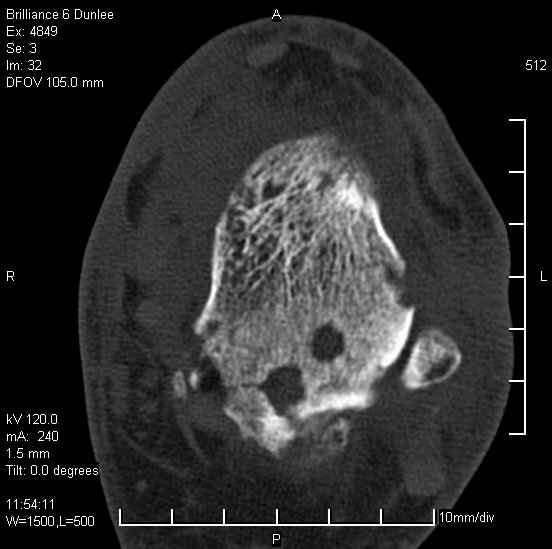

На лечении находится пациент 35 лет. Травма в сентябре 2008 г.- открытый вывих таранной кости

В день травмы ПХО, вправление вывиха, трансартикулярная фиксация. Рана зажила первично. С января нагрузка на конечность. С конца апреля- болевой синдром. На рентгенограммах и КТ признаки ас. некроза таранной кости, артроз подтаранного и голеностопного суставов.

У больного тотальный ас. некрох блока таранной кости, заинтересованы голеностопный и подтараный суставы. Эндопротезирование маловероятно на некротизированную кость. Изолированный подтаранный артродез таран не спасет.При артродезе всю некротизированную кость придется убрать.А далее замещение либо за счет большеберцовой кости, или удлинение на регенерате.